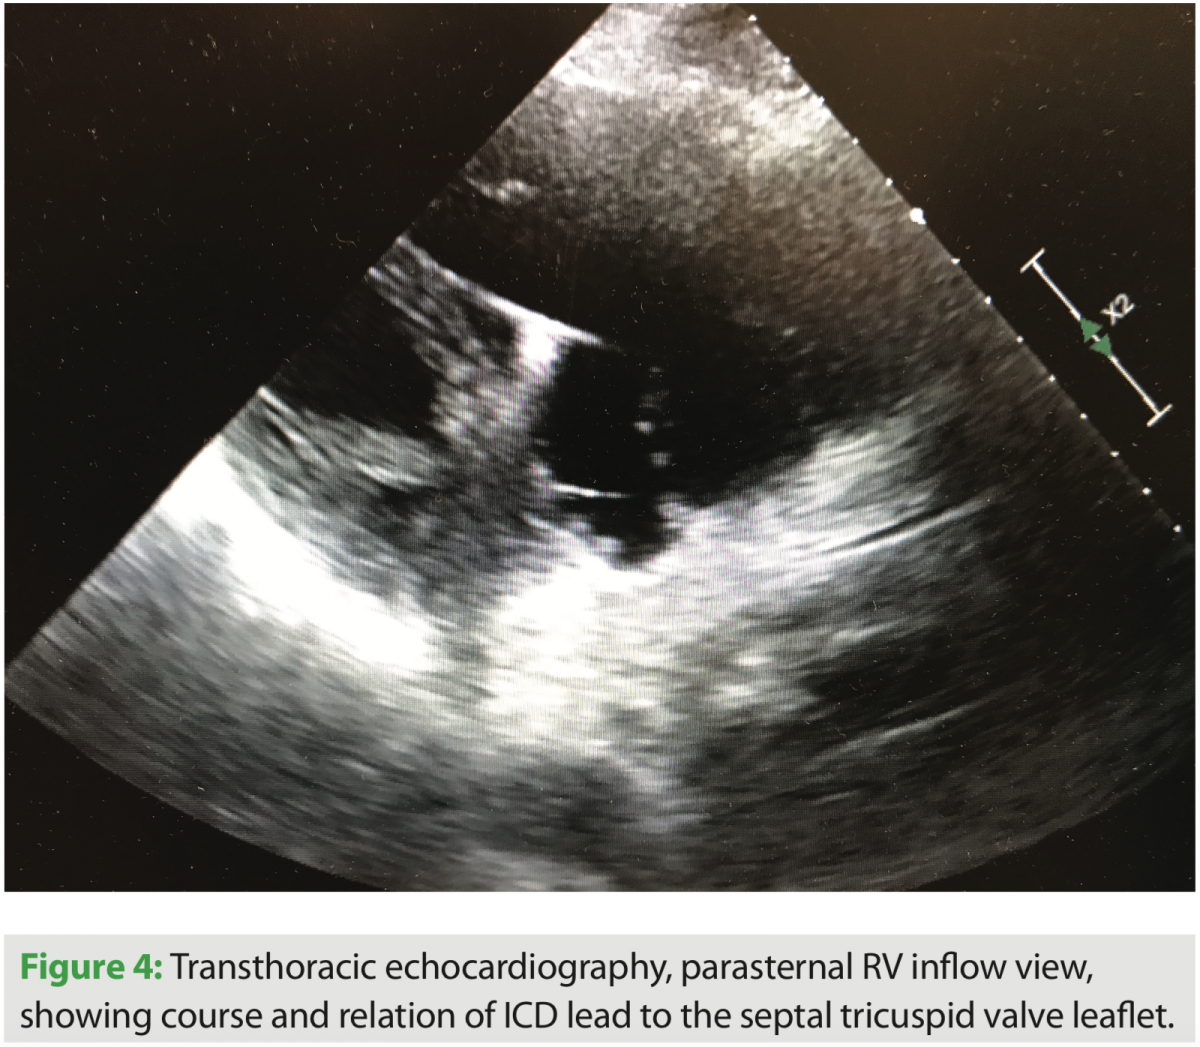

After admission and diuresis, significant symptomatic improvement occurred, and the patient was nearing his perceived dry weight based on initial clinic visits and recorded weights from home. Standard two- and three-dimensional transthoracic echocardiography were performed, and significant tricuspid valve regurgitation was seen. The course of the right ventricular lead can be seen in several views, along with its interaction with the TV leaflet and interventricular septum (Figures 1, 2, and 4). Corresponding tricuspid valve dysfunction is appreciated with severe tricuspid valve regurgitation on Doppler echo images (Figures 3 and 5). The RV was felt to be moderately dilated with a mid-RV diameter of 3.5 cm. Significant RV systolic dysfunction was seen and felt to be moderate with a tricuspid annular plane systolic excursion (TAPSE) of 1.25 cm. The tricuspid valve regurgitation was severe with a vena contracta width of 0.9 cm and PISA radius of 1.0 cm. LV systolic function was essentially unchanged, with an EF of 25%. The bioprosthetic aortic valve was well seen and without significant dysfunction.